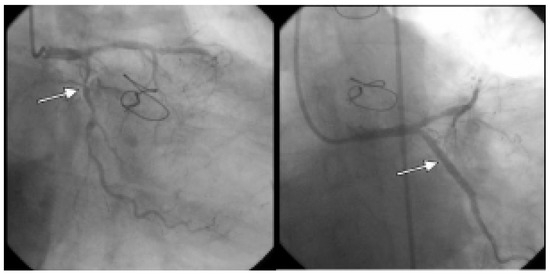

Progrediente Herzinsuffizienz Trotz Biventrikulärer Stimulation

by C. Bösch, B. Schaer and S. Osswald

Drei Monate nach Implantation eines CRTGerätes hatte sich die Dyspnoe des Patienten von NYHA IV auf NYHA II verbessert [...] Full article

Show Figures

Figure 1